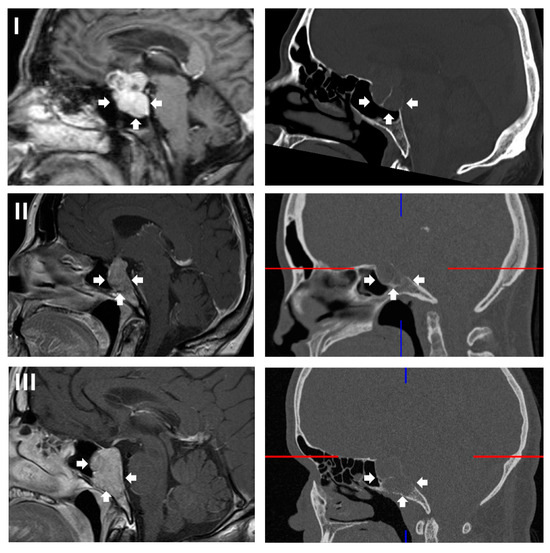

A total of 557 surgeries for pituitary neuroendocrine tumors in an endonasal endoscopic transsphenoidal technique performed between 1 January 2015 and 31 August 2025 at the Department for Neurosurgery at Ulm University, Germany, were reviewed, and 13 cases (2.3%) were identified with predominantly sellar or infrasellar growth and extension into the clivus. Giant adenomas with diffuse infiltration into the clivus but also all other areas of tumor circumference were not included (for examples of tumors primarily extending below the sella, see Figure 1). Due to the often highly irregular and nodular suprasellar tumor growth, volumetry was not used to qualify the tumor as primarily extending below the sella and into the clivus. To qualify for an inclusion, more than 50% of the tumor mass was required to be within and below the sella, with only minor suprasellar nodules in relation to the tumor mass.

Figure 1. Examples of lesions included in this retrospective study. All lesions showed predominantly a growth from the sella into the clivus. While some tumors only spread from the sella inferiorly (A,B), others also demonstrated a minor growth into the suprasellar region (C). Infiltration of the sphenoid sinus is present in all three examples. The tumor extension is highlighted by white arrows.